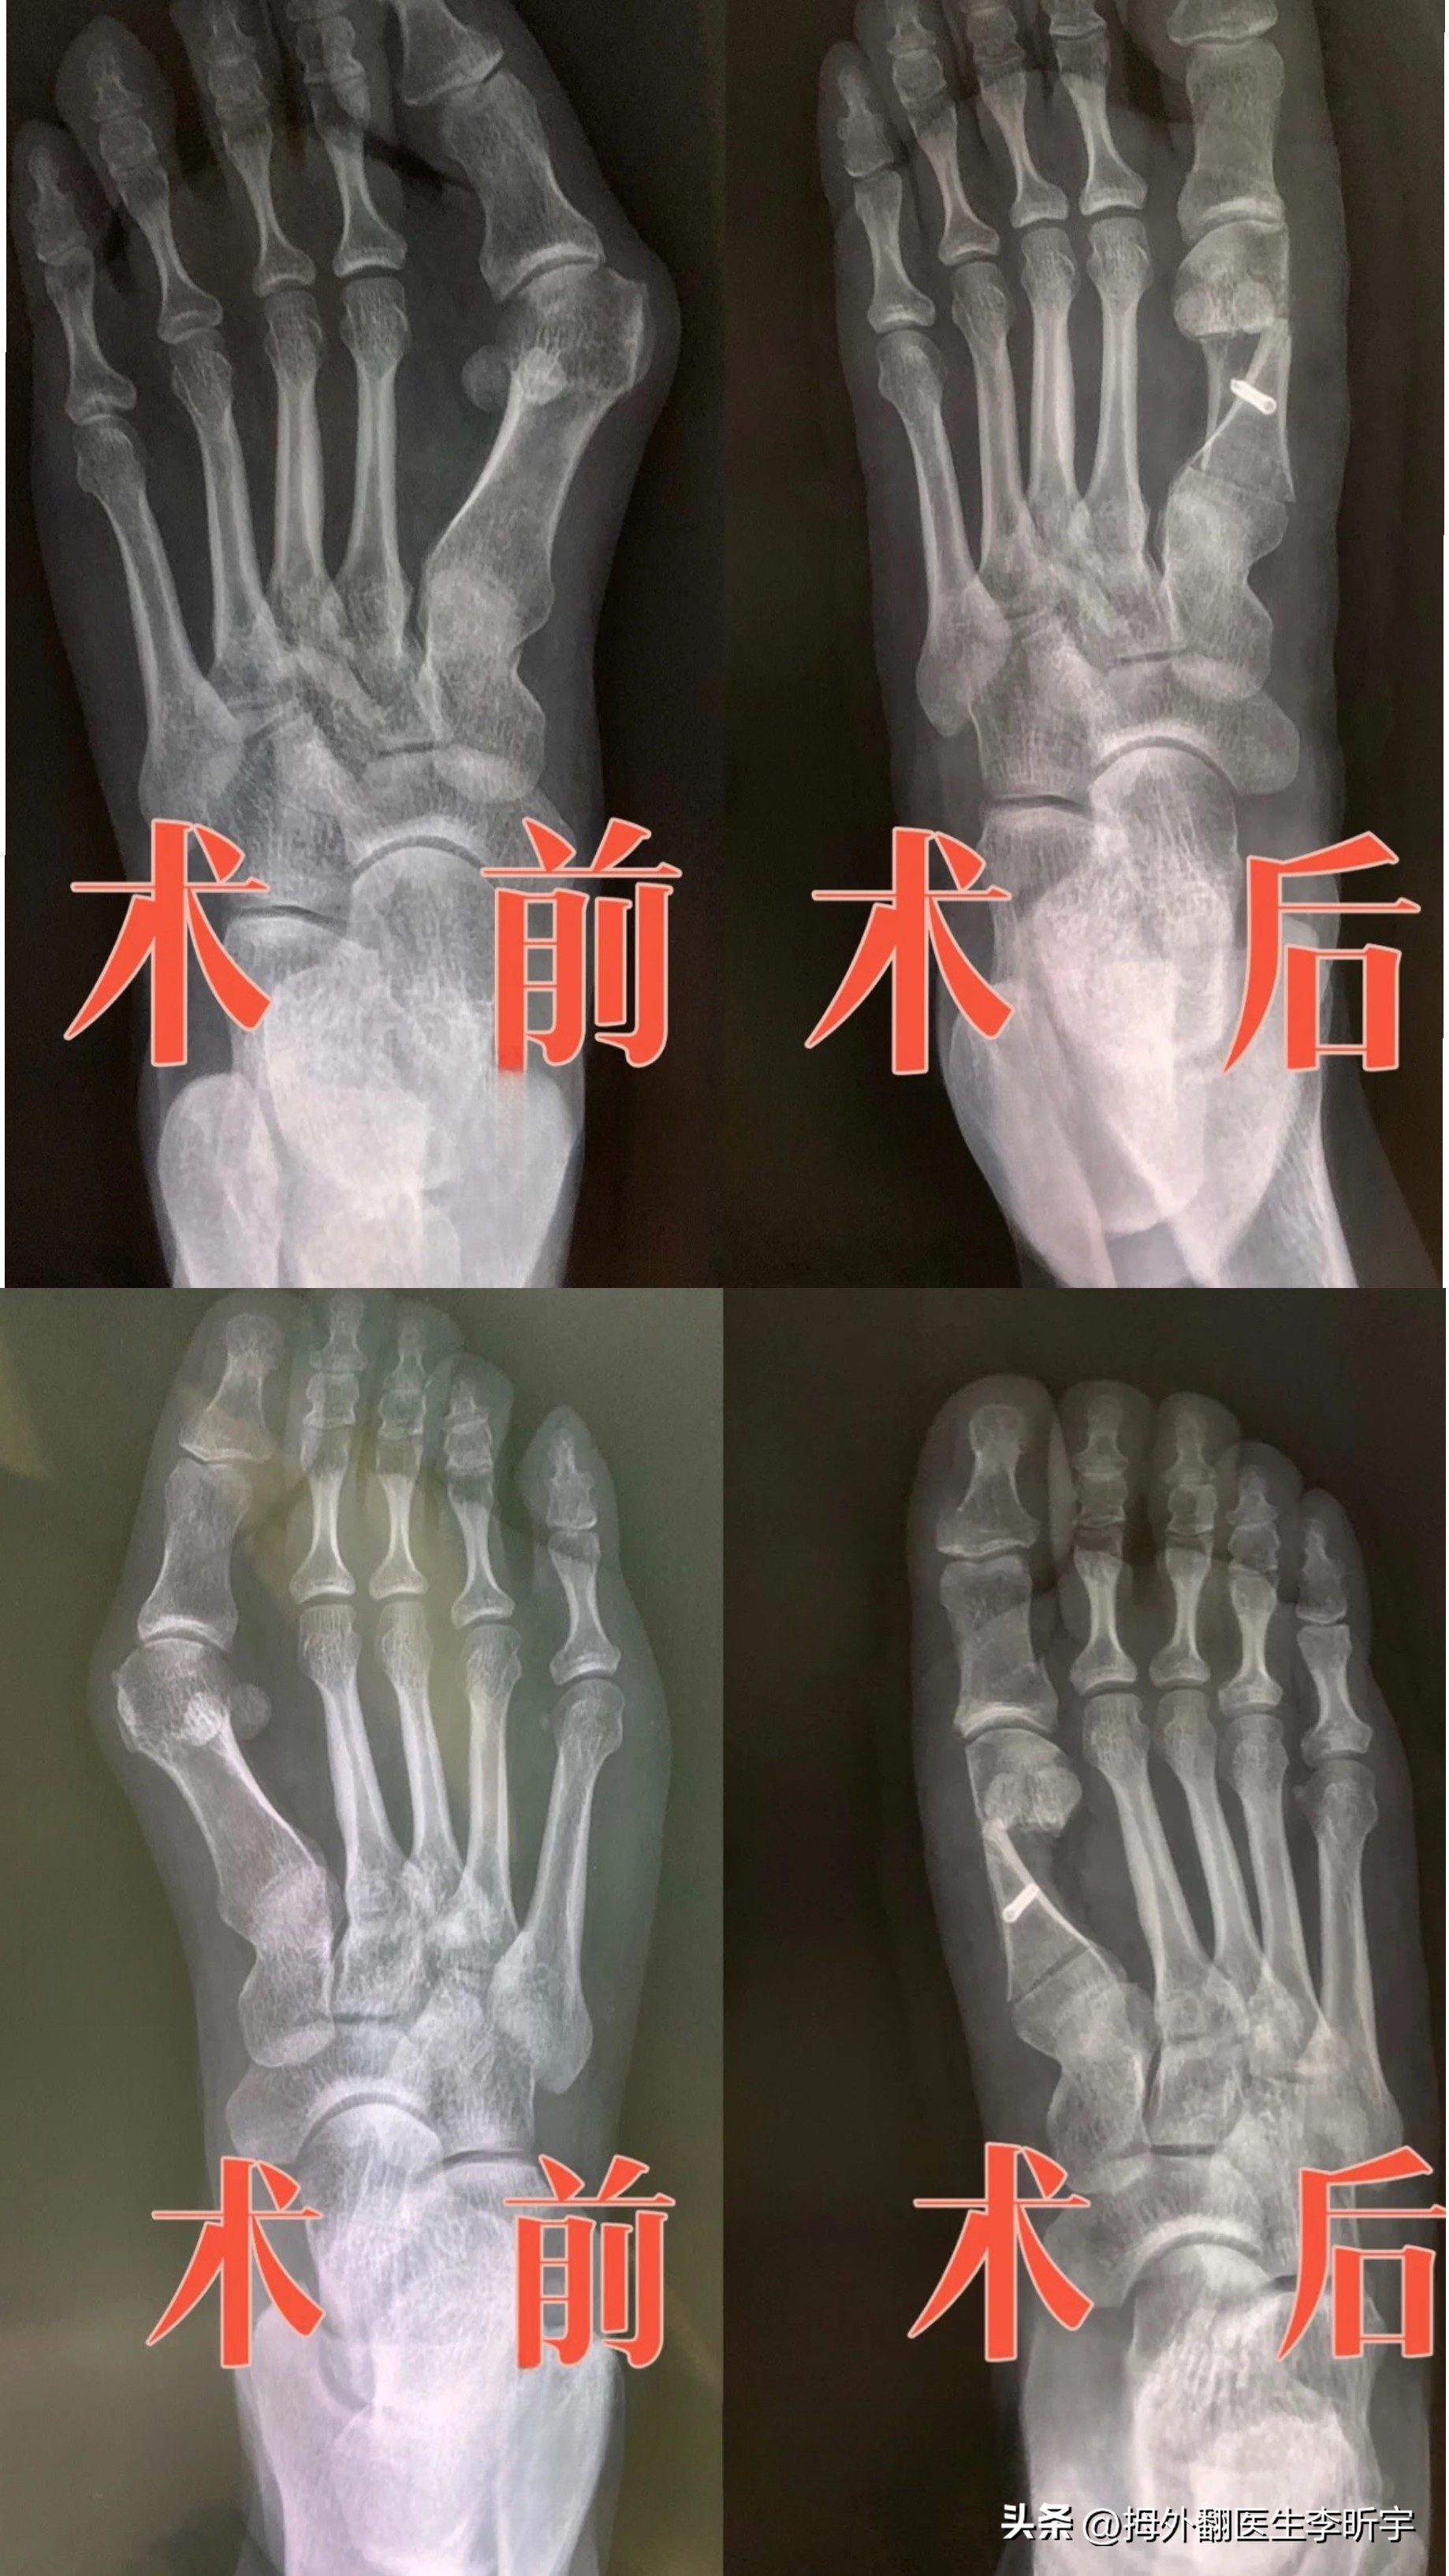

这位患者的脚其实很严重,鼓包很明显,并伴有疼痛。据张女士说道:大脚骨问题困扰了她很久,也是经历了一个从轻到重的过程,期间有过长时间走路鼓包处会间歇性疼痛的情况,但是一直没有当回事。

今年让她决定手术最大的原因是她的右脚以前不是很严重,但是发展到现在两只脚都鼓起包了,这个趋势可不太妙;其次她发现好久没有买到过合适的鞋子了,再宽的运动鞋都会撑出鼓包,漂亮的凉鞋、拖鞋更是再没穿过了,去买鞋的时候也会受到异样的眼光。因为脚确实很自卑,不敢露出来。